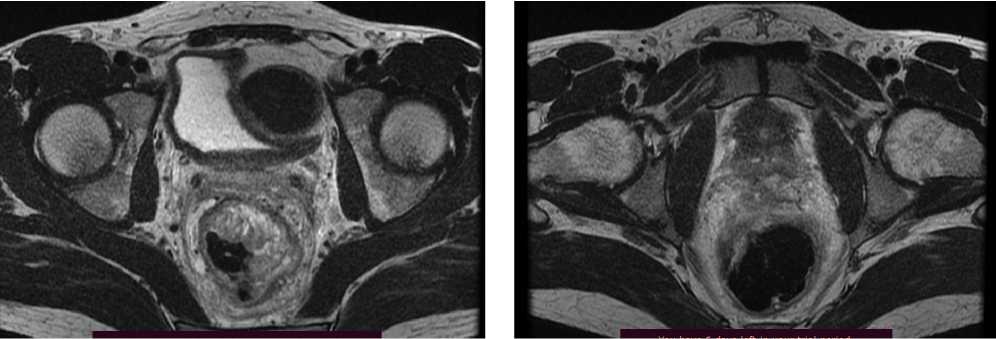

Клинический случай 3. Пациент Е., 37 лет. В июле 2022 г., в связи с дообследованием по поводу генеза кровянистых выделений из прямой кишки, выполнена ректороманоскопия, по результатам которой выявлено образование среднеампулярного отдела прямой кишки. По результатам гистологического исследования материала выявлена аденокарцинома толстой кишки, low grade.

При КТ органов брюшной полости и магнитно-резонансная томография (МРТ) органов малого таза (ОМТ) от августа 2022 г. визуализированы патологические образования в печени метастатического характера (n = 8), расположенные билобарно, и образование средне/верхнеампулярного отделов прямой кишки mrT3d/T4aN2 (CRM+ за счет прилежания лимфатического узла/EMVI+). По результатам молекулярно-генетического исследования обнаружена мутация G13D в 13 кодоне гена KRAS.

Диагноз был установлен как рак среднеампулярного отдела прямой кишки сТ4аN2M1 (hep).

По решению онкологического консилиума пациенту начат ПХТ 1 линии в режиме FOLFOX + бевацизумаб. С 02.09.2022 проведено 3 цикла ПХТ 1 линии, по результатам контрольных обследований зарегистрировано прогрессирование процесса за счет роста образований печени до 64 × 46 мм и появления линзовидного образования между передней поверхностью прямой кишки и задней поверхностью предстательной железы размерами 47 × 15 × 25 мм (рис. 7, 8).

Рис. 7. Результаты компьютерной томографии органов брюшной полости у пациента 37 лет с диагнозом метастатический колоректальный рак с признаками микросателлитной нестабильности (октябрь 2022 г., после 3-х циклов FOLFOX + бевацизумаб)

Fig. 7. Results of abdominal CT scan in a 37-year-old patient diagnosed with metastatic MSI-H colorectal cancer (October 2022, after 3 cycles of FOLFOX + bevacizumab)

Рис. 8. Результаты магнитно-резонансной томографии органов брюшной полости у пациента 37 лет с диагнозом метастатический колоректальный рак с признаками микросателлитной нестабильности (октябрь 2022 г., после 3-х циклов FOLFOX + бевацизумаб)

Fig. 8. Results of abdominal MRI in a 37-year-old patient diagnosed with metastatic MSI-H colorectal cancer (October 2022, after 3 cycles of FOLFOX + bevacizumab)